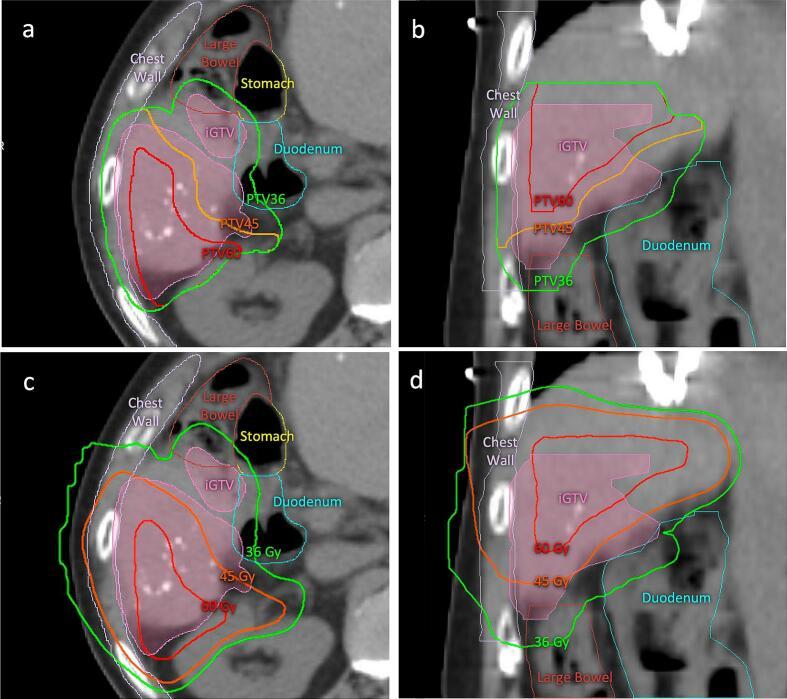

Although simultaneous integrated boost and protection with proton beam therapy (SIB-PBT) facilitates tumor dose escalation while maintaining organ-at-risk (OAR) dose constraints, clinical outcomes are limited. This study assessed the safety and efficacy of using the SIB-PBT technique in hepatocellular carcinoma (HCC) patients.

We reviewed 47 patients with HCC who underwent SIB-PBT between 2014-2021. The radiation dose ranged from 36-67.5 Gy(RBE) in 15 fractions. SIB-PBT was used for the following reasons: minimize high-dose exposure to organs-at-risk (OARs) (n = 22, 47 %), treat targets with different dose levels (n = 6, 13 %), or both (n = 19, 40 %). Survival, local control, and toxicities were assessed using Kaplan-Meier, Fine-Gray cumulative incidence, and descriptive statistics, respectively.

Forty-one patients (87 %) had tumors located ≤2 cm from luminal gastrointestinal (GI) OARs. The median tumor diameter was 9.2 cm (range, 2.0-21.5 cm). The median EQD2 D50%, D95% and D99% of gross tumor volume were 79.8 (range, 51.1-85.9), 66.7 (range, 36.9-84.6) and 50.2 (range, 34.1-83.6) Gy(RBE), respectively. Most patients (91 %) received a D0.5 cc of <45 Gy(RBE) to luminal GI OARs. At a median follow-up of 22 months (range, 0.8-77.0 months), the 2-year cumulative incidence of local failure was 12 %. The 2-year progression-free survival and overall survival rates were 12 % (95 % CI 4.7-23.4 %), and 49 % (95 % CI, 33.2-63.2 %), respectively. One patient experienced grade 3 acute nausea/vomiting. No GI bleeding/ulcers or grade 4 + toxicity were observed. CP + 2 occurred in 5 patients.

SIB-PBT enables OAR protection along with heterogeneous tumor dose escalation and is a safe and effective treatment for HCC tumors.